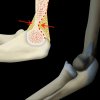

Supracondylar Fracture | X-ray

Simple x-ray interpretation of a supracondylar fracture and its mechanism of injury.